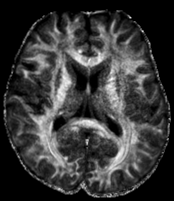

3.2.3 Example 2: Diffusion-weighted MRI (dMRI)

DMRI is an important MRI technique to study the neural architecture and connectivity of the brain. It is based on obtaining multiple 333-dimensional diffusion-weighted images to investigate the water diffusivity along various directions, being clinically important especially for the investigation of brain disorders, see e.g. (citep \@BBN(Shenton et al., 2012)). However, low signal-to-noise ratio and acquisition time limit the spatial resolution of dMRI and therefore its usage is currently mainly restricted to medium-to-large white matter structures, whereas very small cortical or sub-cortical regions cannot be traced accurately. To overcome this, several methods for increasing the spatial resolution of dMRI have been introcuded, see e.g. (citep \@BBN(Dyrby et al., 2014; Van Steenkiste et al., 2016; Grieve and Maller, 2017)).

Here, we study image data from an acquisition and reconstruction scheme for obtaining high spatial resolution dMRI images using multiple low resolution images, cf. (citep \@BBN(Ning et al., 2016)). The suggested method combines the concepts of compressed sensing and super-resolution to reconstruct high resolution diffusion data while allowing faster scan time. The data is visualized via the fractional anisotropy (FA) measures computed using diffusion tensor imaging (citep \@BBN(Basser, Mattiello, and LeBihan, 1994)).

The data from a human subject was acquired from a MGH connectome 3T scanner. Three thick-slice diffusion weighted imaging (DWI) volumes with voxel size 0.9×0.9×2.7mm30.90.92.7𝑚superscript𝑚30.9\times 0.9\times 2.7mm^{3}, TE/TR = 84/7600ms847600𝑚𝑠84/7600ms and 606060 gradient directions at b=2000s/mm2𝑏2000𝑠𝑚superscript𝑚2b=2000s/mm^{2}. A separate low-resolution isotropic DWI with a spatial resolution of 1.8×1.8×1.8mm31.81.81.8𝑚superscript𝑚31.8\times 1.8\times 1.8mm^{3} and with 606060 gradient directions at b=2000s/mm2𝑏2000𝑠𝑚superscript𝑚2b=2000s/mm^{2}.

The super resolution image in 6(a), serving as a reference here, was obtained using the super-resolution reconstruction technique that combines multiple thick-slice DWI with all 60 diffusion directions into a high-resolution image, cf. (citep \@BBN(Ramos-Llordén et al., 2020)). This technique yields a high quality image with good detail preservation, but takes much longer scan time than the standard upsampling method in 6(c), where the FA map of the low-resolution data was up-sampled using 3DSlicer (citep \@BBN(Fedorov et al., 2012)) to the higher resolution.

The image in 6(b), cf. (citep \@BBN(Ning et al., 2016)), was obtained using a combined super-resolution reconstruction, compressive sensing, and spatial regularization techniques with thick-slice images, where each thick-slice DWI has a different set of 202020 diffusion gradient directions, saving indispensable scan time. The advanced method yields a much higher visual quality image than 6(c), preserving more anatomical details.

Refer to caption

(a) Reference

(b) (17.62, 0.57, 0.19)

(c) (18.23, 0.58, 0.26)

Figure 6: Visualized FA images obtained from diffusion MRI with super-resolution reconstructions. The up-sampled image (c) is wrongly judged to have better quality than the high-resolution reconstruction (b) by PSNR and SSIM, LPIPS judges this task correctly.

FR-IQA mismatch

We can see in Figure 6 that PSNR and SSIM misjudge the visual quality of the high-resolution reconstruction in (b) in comparison to the up-sampled image in (c). Clearly, that image has worse visual quality than the one in (b). It is per default more blurry and does not provide sufficient anatomical details. LPIPS yields more sufficient results in this example, and correctly attributes (c) a higher quality error.

In this example it has to be noted that the computed IQA numbers are generally quite low, because the resulting FA images do not necessarily have to have the same range or distribution as the reference image. Therefore, in order to compare the reconstruction quality directly, this task generally benefits from NR-IQA evaluation.